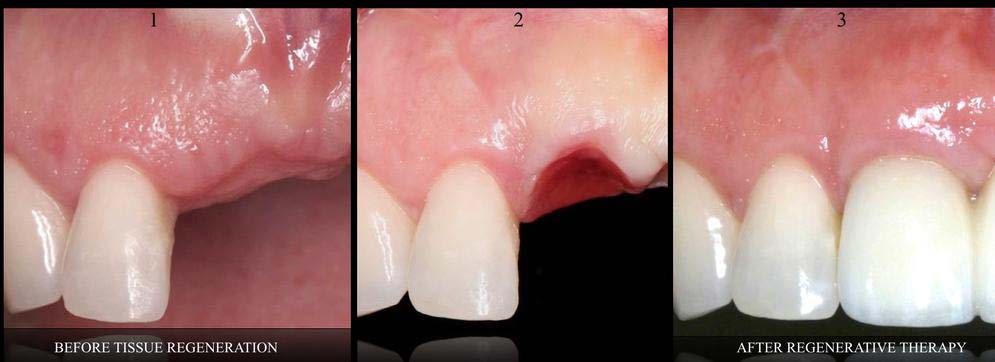

- GUIDED BONE & TISSUE REGENERATION

- GUM REGENERATION/GRAFTING FOR RECEDING TISSUES --> GINGIVAL RECESSION THERAPY